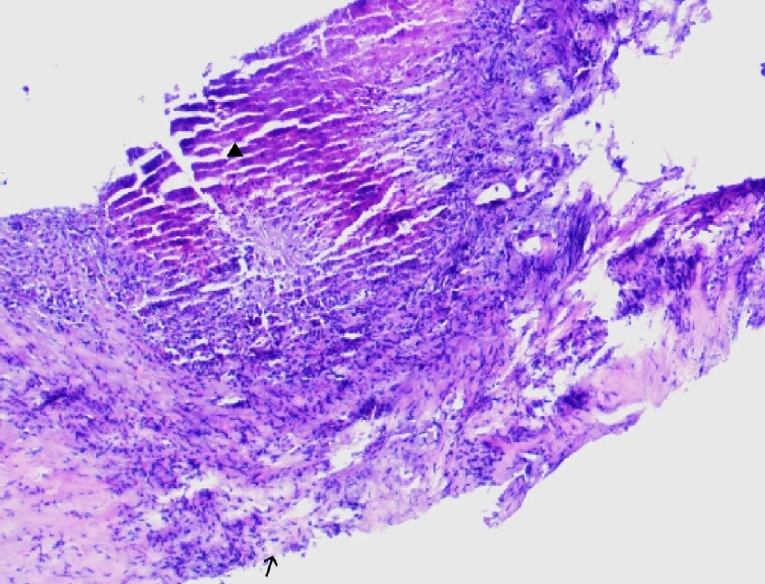

Ultrasound showed a heterogeneous hyperechoic mass (7.8×5.5 cm) with unclear borders in liver segments S4, S7, and S8 (Fig. 1). Computed tomography suggested a large, poorly defined mass with mixed density and patchy calcifications (maximum cross-sectional area 15.11×11.29 cm) in the liver. No enhancement was observed in dynamic contrast imaging. A low-density lesion in the left adrenal gland showed no enhancement (Fig. 2A). The right portal vein was narrowed. The right and middle hepatic veins were partially obscured in the portal venous phase (Fig. 2B). The presence of a large, infiltrative mass with heterogeneous density and irregular calcifications is a recognized, though not universal, imaging presentation of advanced alveolar echinococcosis, which can mimic malignancy.

Fig. 1.

Abdominal color doppler ultrasound showed a heterogeneous.

Fig. 1. Abdominal color doppler ultrasound showed a heterogeneous.